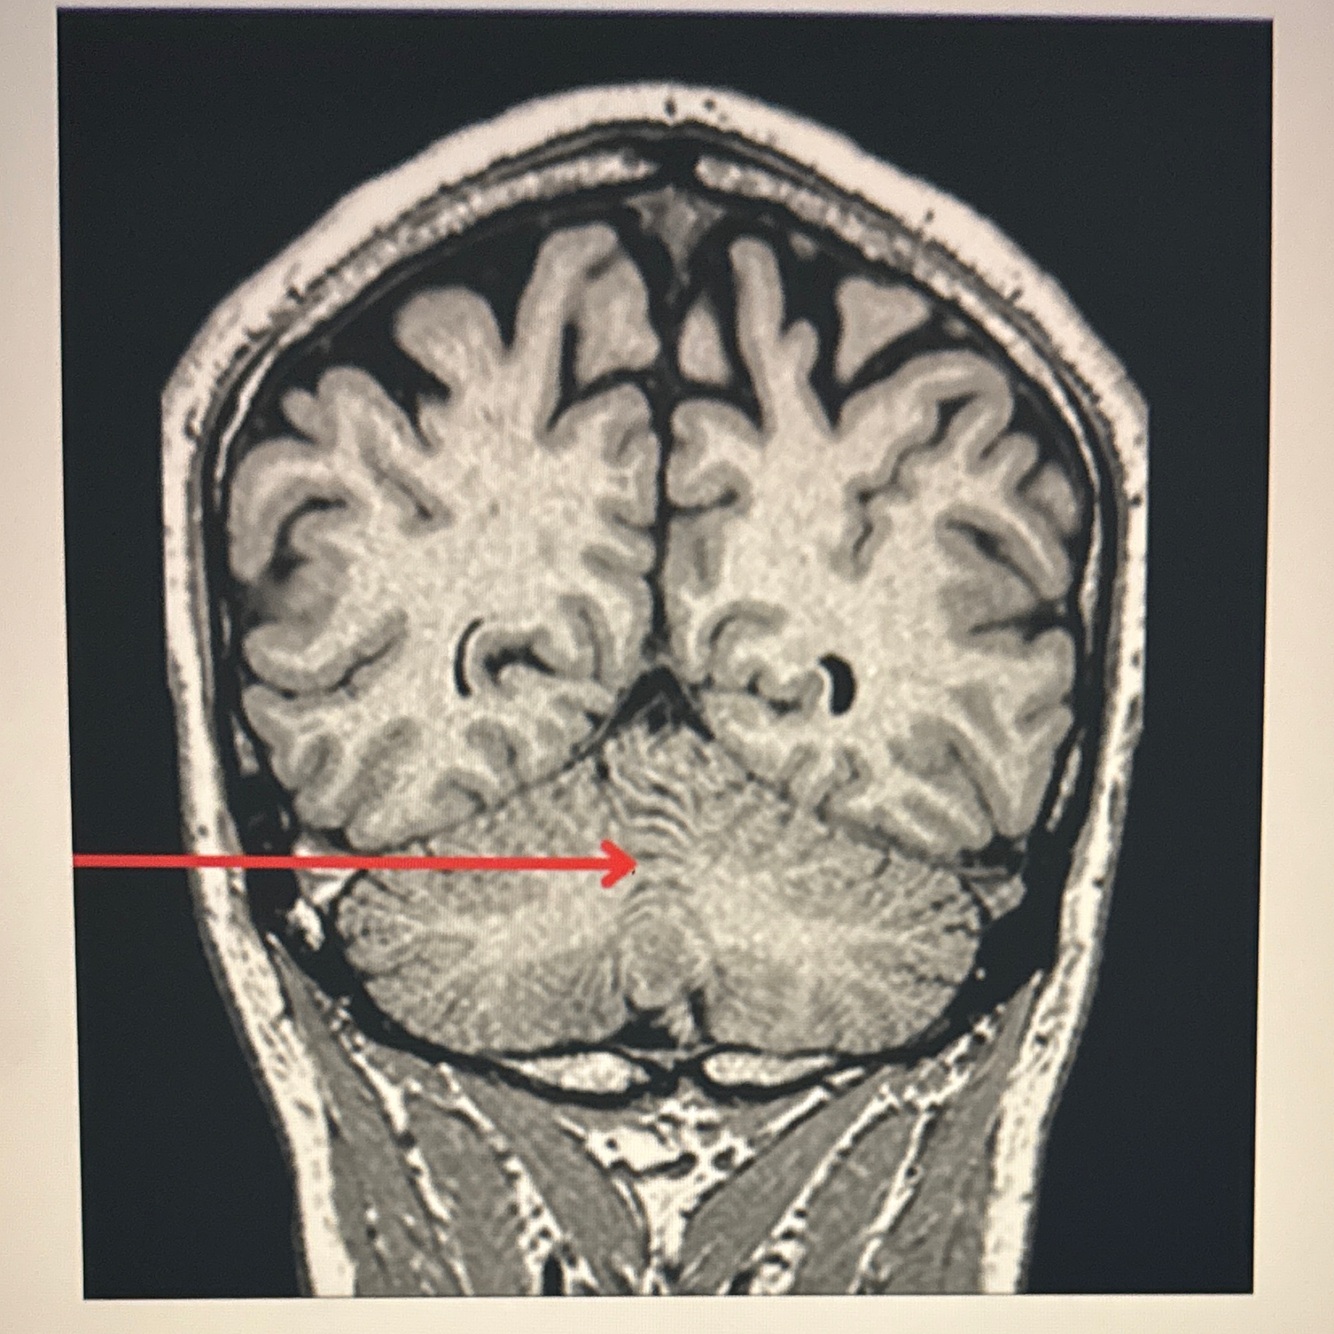

9

Q

A. Epidural hematoma

B. Subarachnoid hemorrhage

C. Intracerebral hemorrhage

D. Subdural hematoma

A